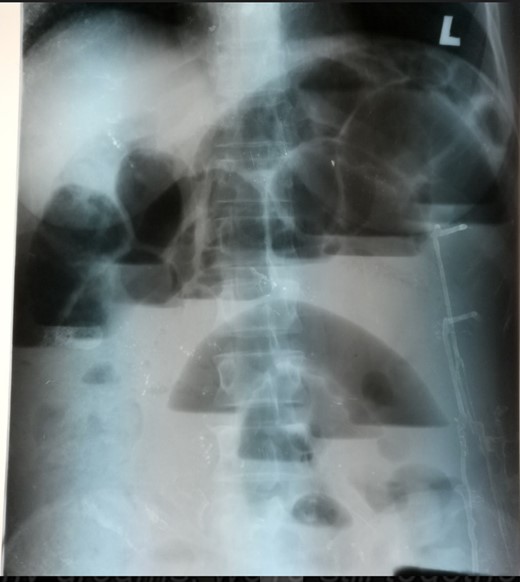

A 46-year-old-female patient presented with crampy abdominal pain of a week duration. Associated with vomiting of ingested matter which latter become bilious matter. She does not pass faeces but passes flatus. She has abdominal distention for last 4 months which increased since the onset of cramp. On physical examination, she was tachycardia to the level of 110 beats per minute, BP 110/70 and she was maintaining her saturation on atmospheric oxygen-97%. Her temperature 37.2°C, her abdomen was distended with hyperactive bowel sound, hyper tympanic to percussion and no tenderness. On digital rectal examination, normal anal tone with empty rectum and no blood on examining finger. On investigation, she has WBC count of 10 600 with neutrophil 86%, She was referred from private setup with abdominal ultrasound which shows significant dilation of bowel loops with increased peristaltic activity and right lower quadrant blind ending tubular structure with diameter of 18 mm with hypoechoic content. On plain abdominal X-ray shows dilated small bowel loops with multiple air fluid level. (Fig. 1)

Erect abdominal X-ray showing multiple air fluid level with dilated small bowel loops.